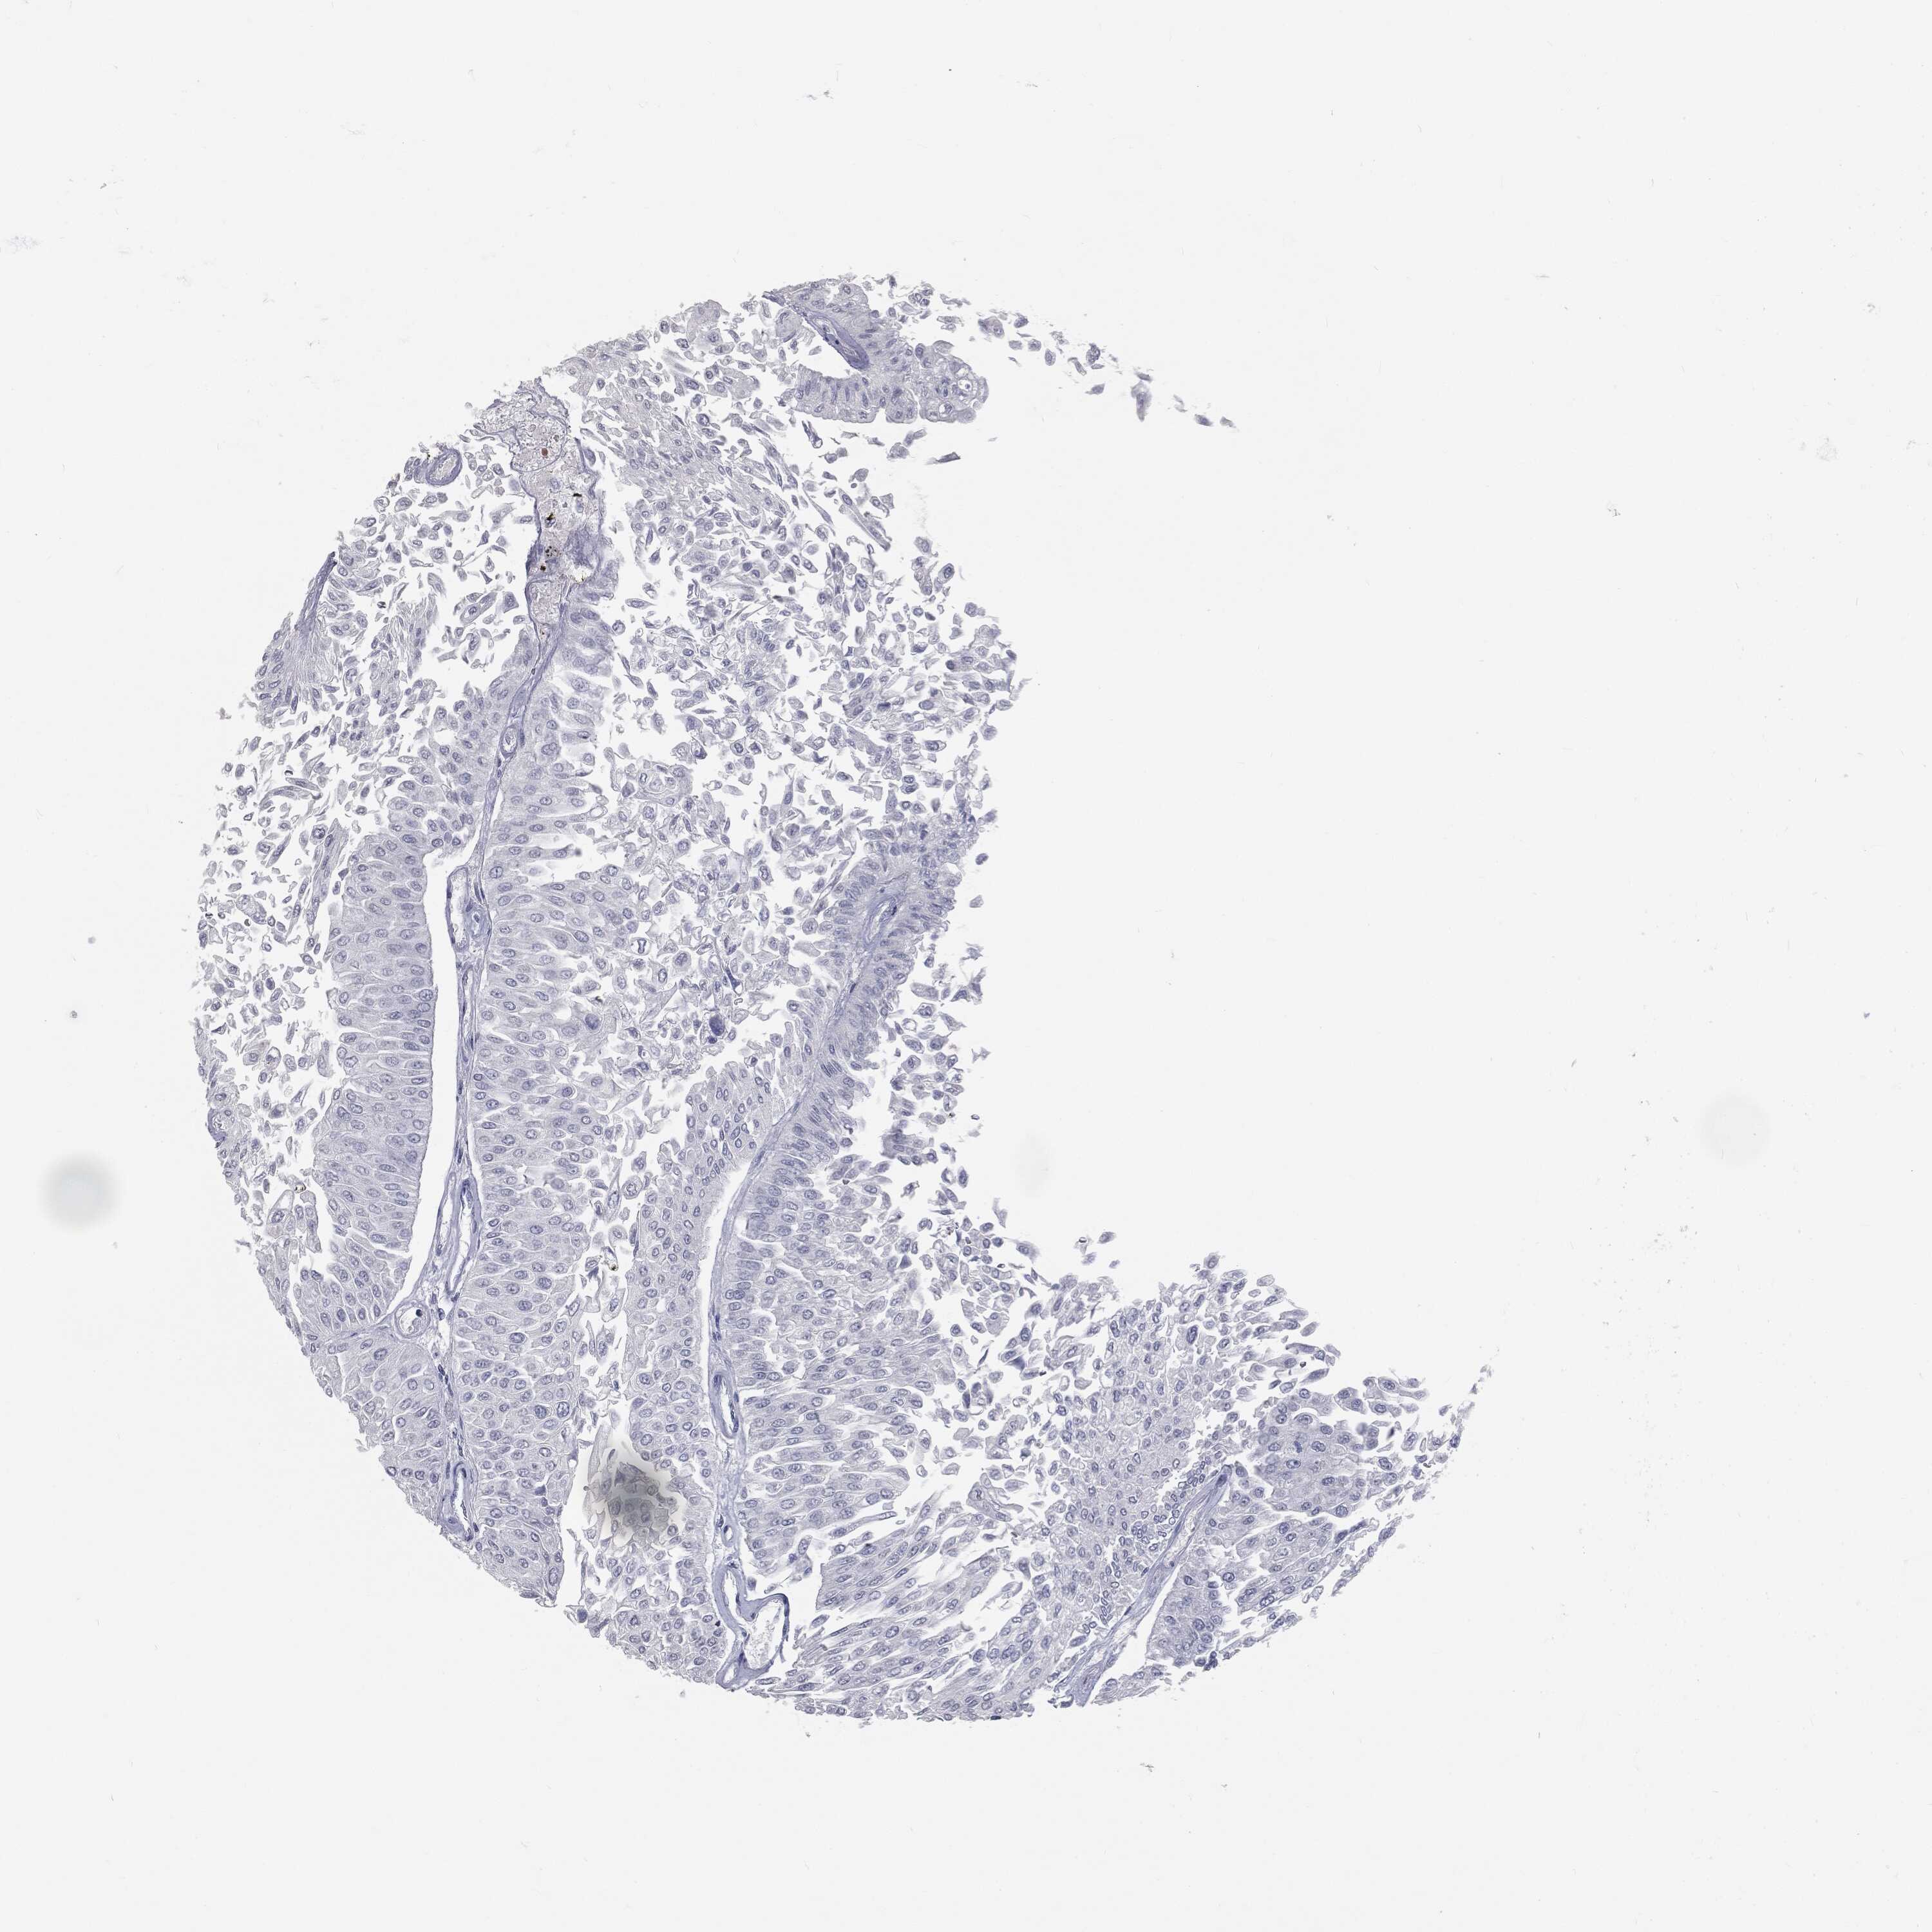

UROTHELIAL CANCER - Protein expressioni

A mouse-over function shows sample information and annotation data. Click on an image to view it in a full screen mode. Samples can be filtered based on level of antibody staining by selecting one or several of the following categories: high, medium, low and not detected. The assay and annotation is described here.

Antibody stainingi

Antibody staining in the annotated cell types in the current human tissue is reported as not detected, low, medium, or high, based on conventional immunohistochemistry profiling in selected tissues. This score is based on the combination of the staining intensity and fraction of stained cells.

Each image is clickable and will lead to virtual microscopy that enables deeper exploration of all samples and also displays staining intensity scores, fraction scores and subcellular localization as well as patient and tissue information for each sample.

Antibody HPA045153

Antibody CAB080138

Urothelial carcinoma, High grade

Urothelial carcinoma, NOS

Urothelial carcinoma, Low grade